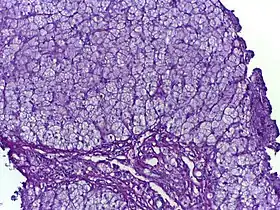

Глікогено́зи (англ. Glycogen storage disease) — група спадкових захворювань, зумовлених дефектами у ферментах та інших білках, що беруть участь у метаболізмі глікогену.